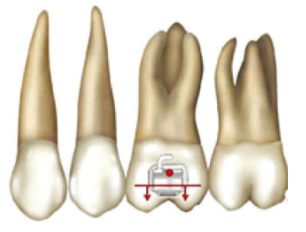

2、双尖牙的托槽要与牙长轴一致,垂直向位置应该在临床冠中心偏向龈方(图3,图4)。